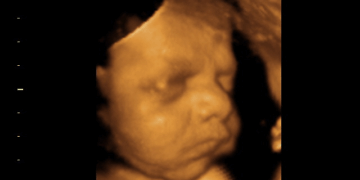

Aborton Activists Claim an Unborn Baby is Merely a ‘Gestator’s’ Body Part